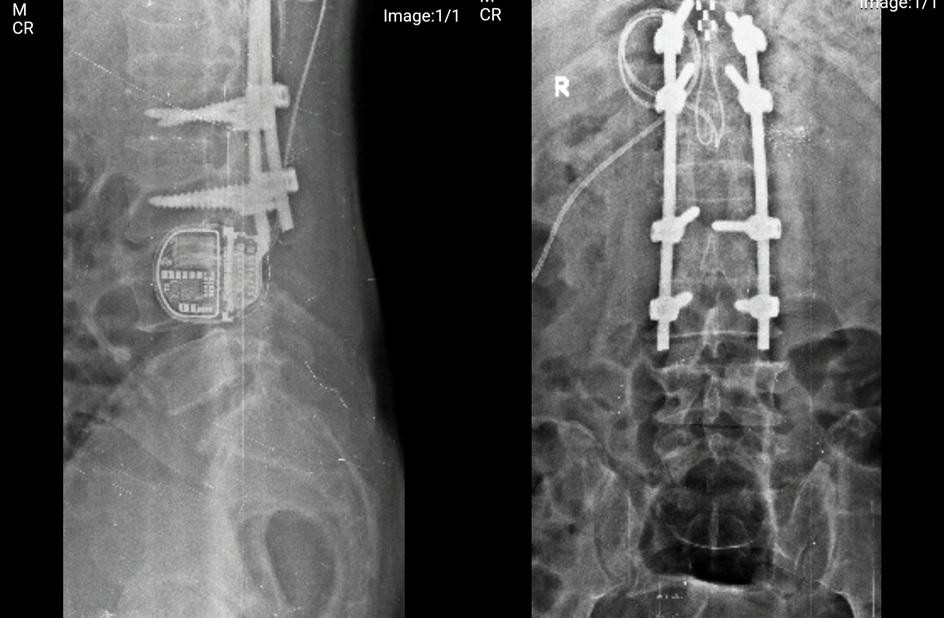

![]() |

| Hình ảnh kiểm tra cho thấy thiết bị điều trị đau có tổng chi phí lên tới 850 triệu đồng trong cơ thể người bệnh |

Bằng điện cực vĩnh viễn phát xung điện, người bệnh sẽ tự điều chỉnh cường độ kích thích tùy theo nhu cầu giảm đau thông qua một thiết bị cầm tay. Sau phẫu thuật, tình trạng đau của bệnh nhân giảm hơn 70%, ông đã có thể tự ngồi và vận động nhẹ.